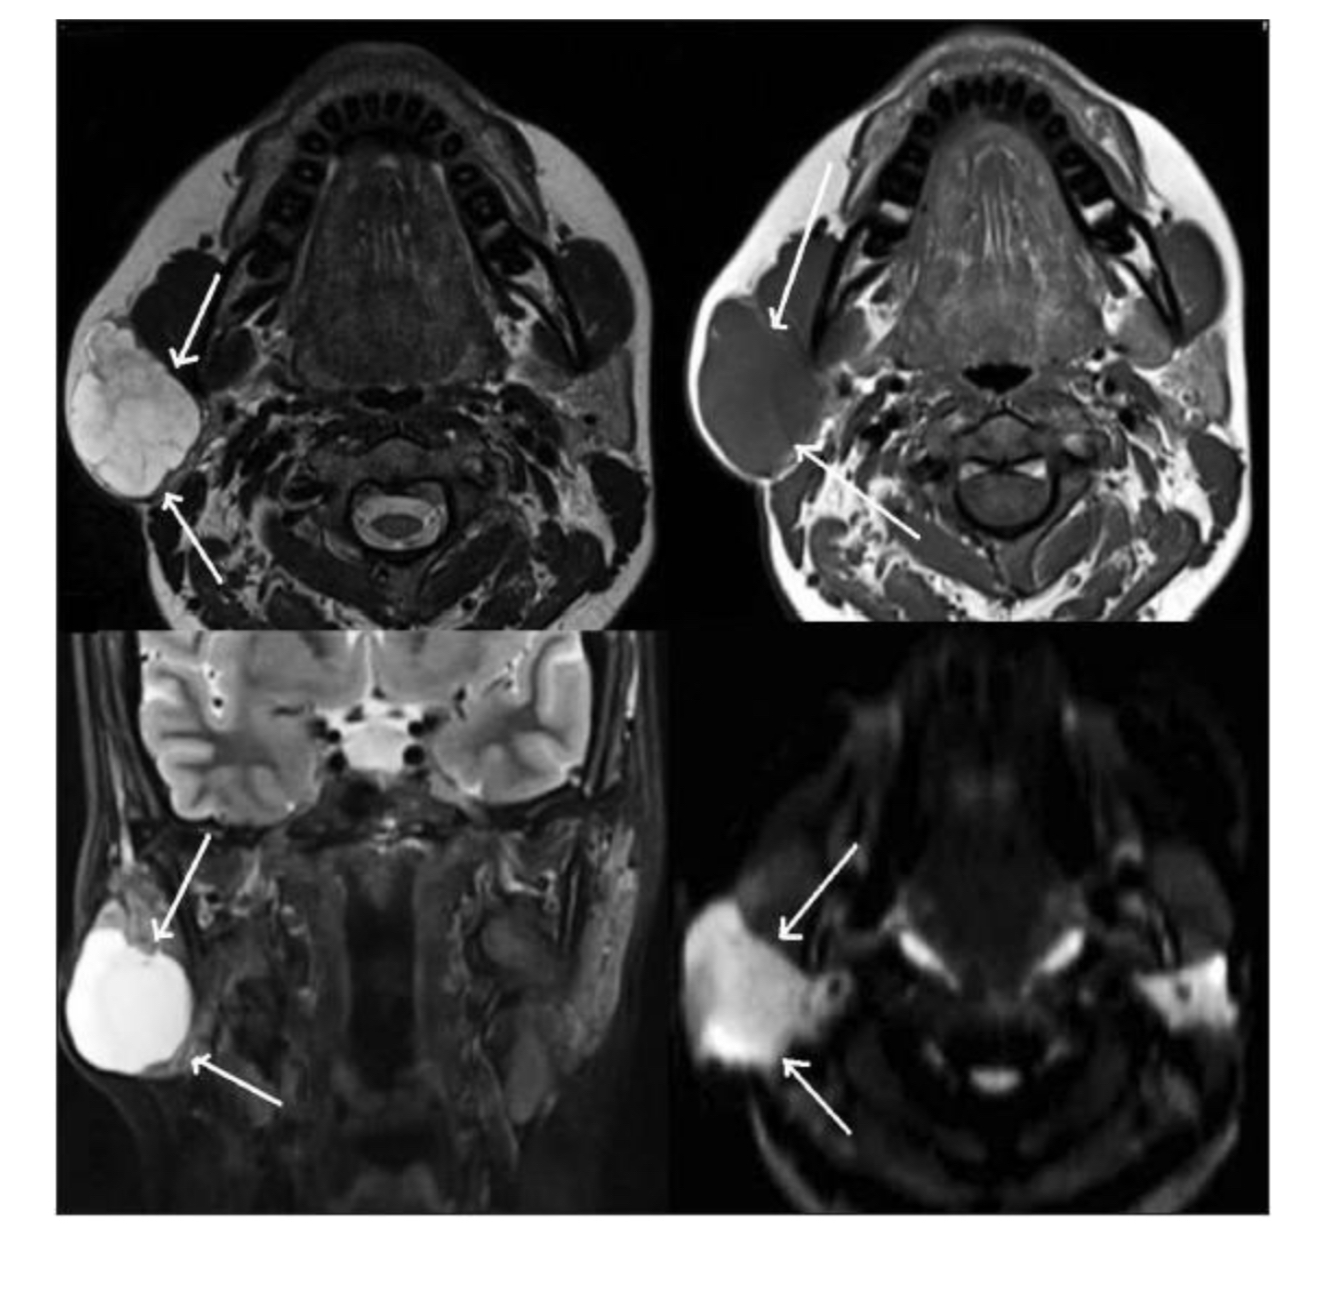

What pathology indicated?

A

Mass - right parotid gland

What does arrow indicate?

left parotid mass

What does arrow indicate ?

submandibular gland

Vocal cord Schwannoma